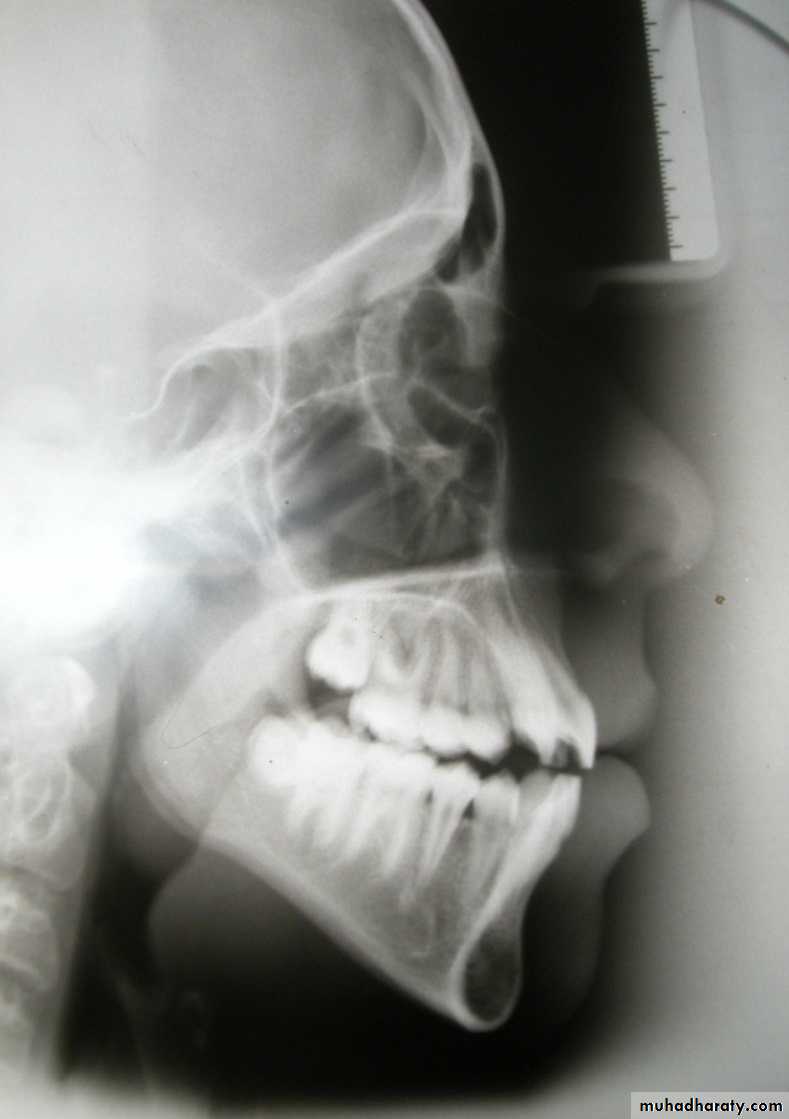

Antero-posterior skeletal relations

ANB angle (3 + 1)Indicates the skeletal relationship between maxilla and mandible:

Large angle = postnormal relation (skeletal class II)

Normal angle = Normal relation

(skeletal class I)

Small angle (reverse) = Prenormal relation (skeletal calss III)

A-B / FOP angle (90 + 5):

Indicates the skeletal relationship between maxilla and mandible with reference to FOP :

Small angle = Prenormal relation

(skeletal calss III)

-1 mm

BO anterior to AOSkeletal AssessmentWits (AO-BO)

(wits= University of Witwatersrand)Facial angle

87° + 3

Indicate the anteropost

Position of the chin